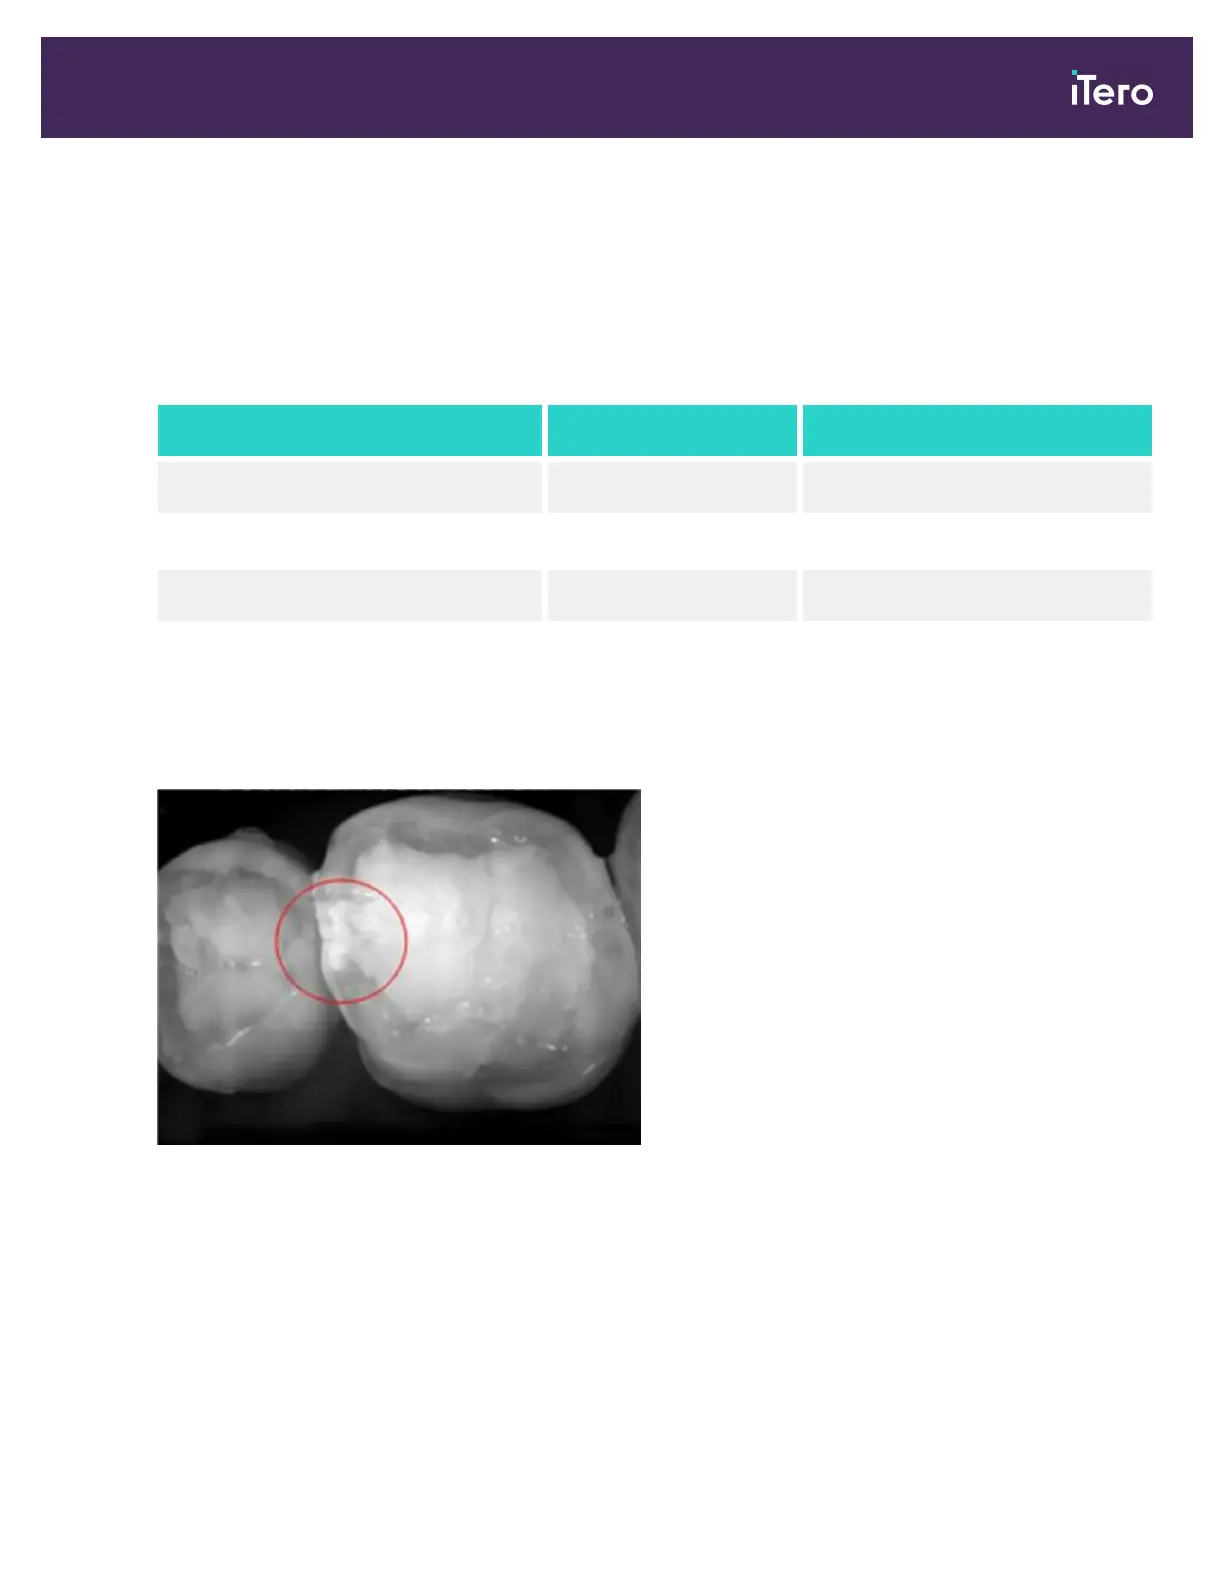

The resulting NIRI grayscale image shows structures with varying translucency as different levels of brightness.

The lower the translucency, the higher the reflection of the infrared light and the brighter the structure. Using this

technology, it is possible to make out the following structures:

The differentiation between carious lesions and dentin is based upon the location of the bright feature. Dentin is

located in the center of a tooth, whereas interproximal carious lesions appear on the interproximal or distal mesial

region, where healthy enamel is expected.

As such, dentin and interproximal carious lesions appear as bright features, with a dark enamel ring around the

dentin structure, as shown in the figure below, which provides an occlusal view of a carious lesion.

Figure 13: Interproximal carious lesion